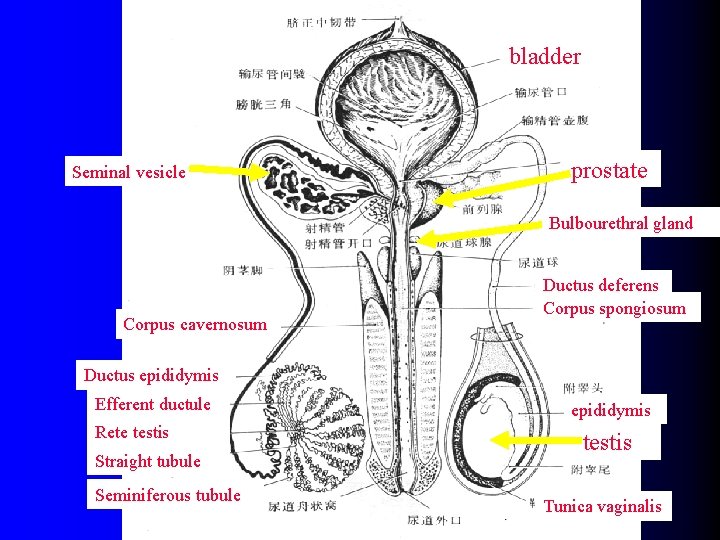

bladder Seminal vesicle prostate Bulbourethral gland Corpus cavernosum Ductus deferens Corpus spongiosum Ductus epididymis Efferent ductule Rete testis Straight tubule Seminiferous tubule epididymis testis Tunica vaginalis